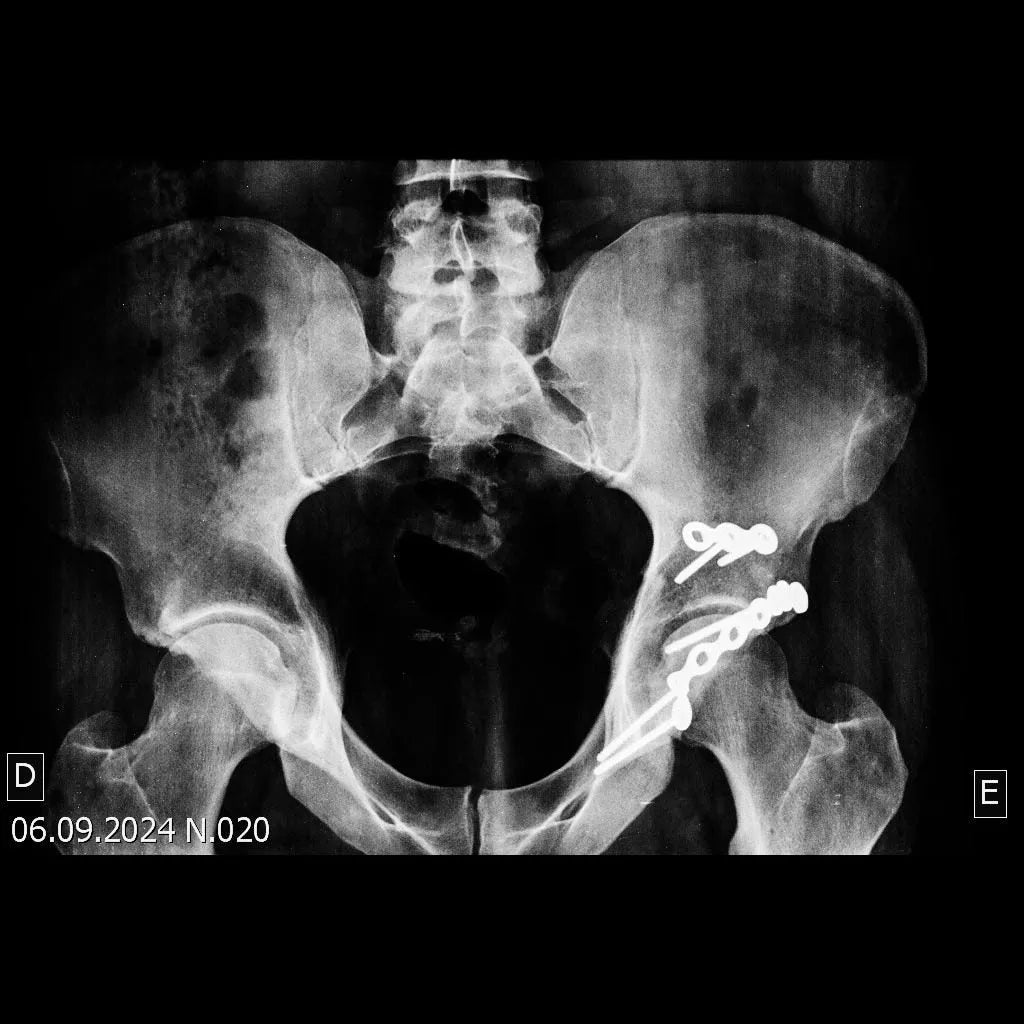

Domine o tratamento de fraturas do rebordo posterior do acetábulo associadas à luxação do quadril. Este treinamento oferece uma imersão técnica em uma abordagem cirúrgica cuidadosamente planejada e executada, visando a redução dos fragmentos, a fixação para restabelecer a congruência articular e a estabilidade do quadril.

- Tratamento cirúrgico de fraturas do rebordo posterior do acetábulo com luxação do quadril.

- Fixação Definitiva com Múltiplas Placas: Aprenda a fixar a placa principal no ísquio, contornando todo o rebordo posterior, com parafusos direcionados para o teto acetabular. Utilize uma segunda placa no vértice do fragmento superior para fixação. Compreenda como a utilização dessas duas placas proporciona redução e estabilidade satisfatórias, eliminando a necessidade de placas em mola.